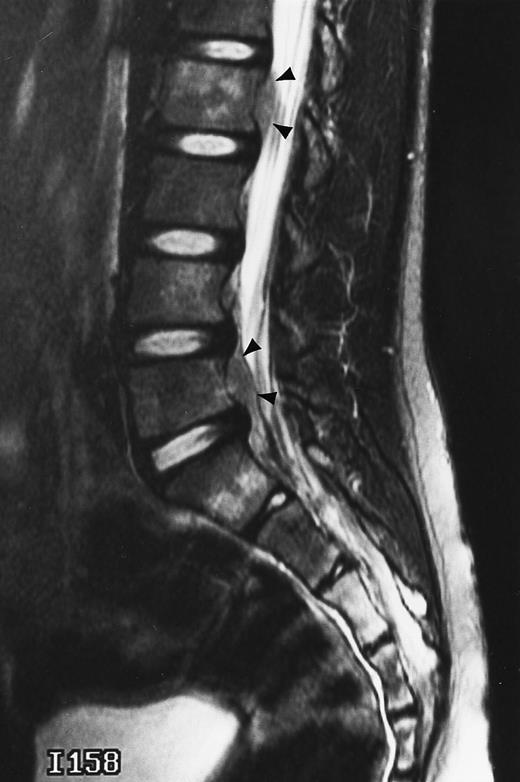

An 8-year-old boy with Burkitt's lymphoma and diffuse marrow involvement. Fat-suppressed, T2-weighted fast spin echo (3000/96, TR/TE) sagittal MR image of the lumbar spine shows heterogeneous signal intensity of the bone marrow and epidural extension of tumor (arrowheads) at the level of L5 and L2, with apparent preservation of the vertebral cortex.